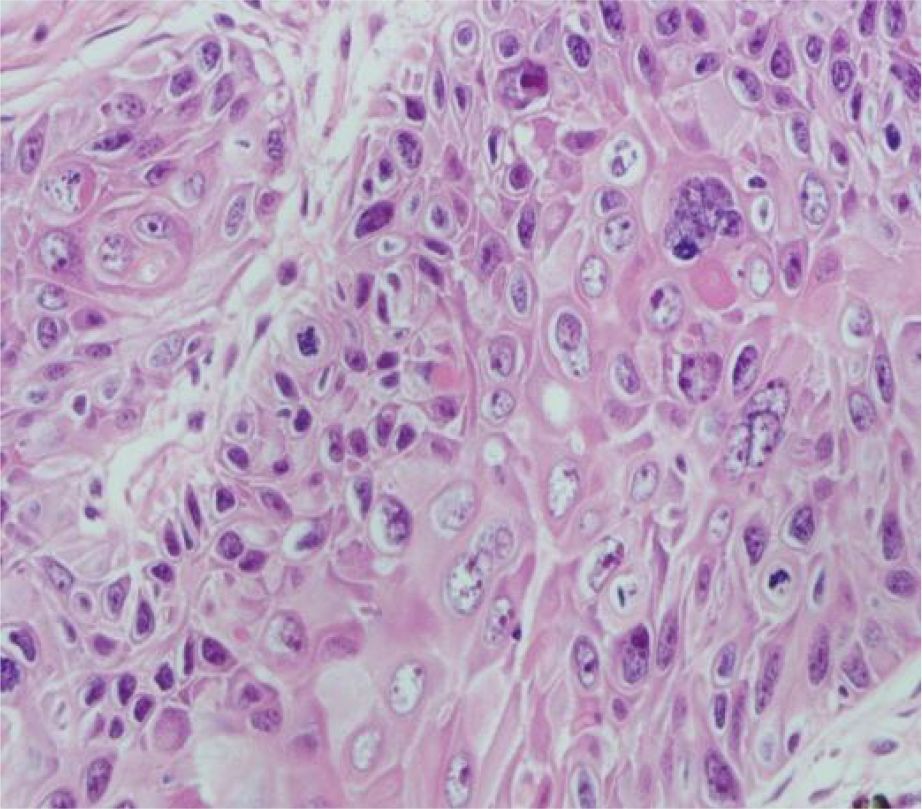

Figure 2

Microscopic view of tissue, stained in various shades of pink and purple, showing densely packed cells with varying nuclei sizes. The texture is irregular, indicating possible pathological changes.

Figure 2. Pathological section.

A 51-year-old middle-aged man inadvertently noticed a soybean-sized swelling on the perianal skin, without obvious symptoms such as itching, pain, or bleeding and discharge. Three months later, the swelling gradually increased in size, accompanied by itching and discharge (Figure 1). A pathological biopsy revealed “perianal” Bowen’s disease (Figures 2, 3), with suspected focal infiltration. After consultation with a surgical team, it was determined that the patient’s perianal tumor had grown significantly, involving the scrotum and perineum, with poor mobility, making radical resection impossible. Following departmental discussion, the patient was treated with tislelizumab and capecitabine chemotherapy, along with topical application of fluorouracil ointment on the tumor. After two cycles of treatment, the tumor was significantly reduced, and the third cycle of treatment was continued (Figure 4). However, the patient did not proceed with the fourth cycle of treatment due to personal reasons. Subsequent follow-ups have shown that the patient has survived for two years since then.